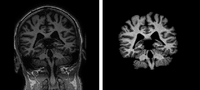

PAR-07-249: R01EB006733 Development and Dissemination of Robust Brain MRI Measurement Tools This project is funded under an NCBC collaboration grant to PI Dinggang Shen at UNC-Chapel Hill. The goal of this project is to develop and widely distribute a software package for robust measurement of brain structures in MR images using computational neuroanatomy methods.More... |